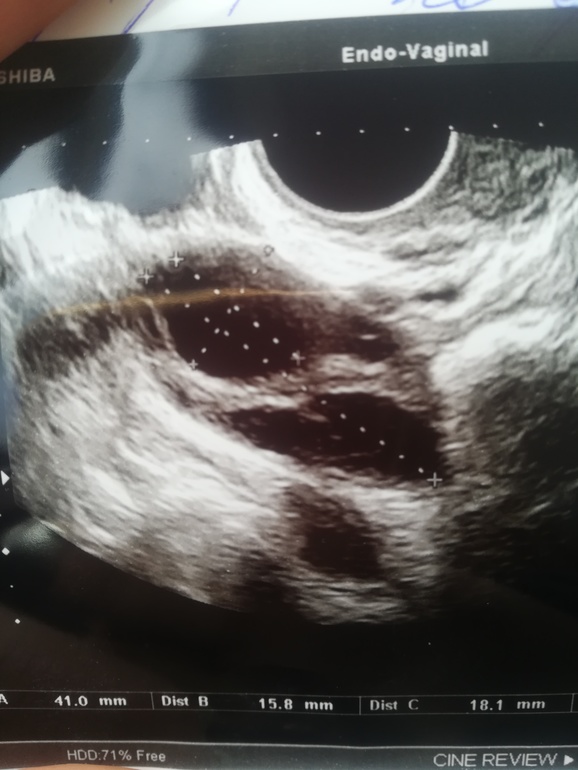

Девочки, кто разбирается в фото? Вот фото 2х яичников . Что вы на них видите? Жт есть ?

Похоже больше на сдувающийся фолликул. Так как форма какая-то расплывшаяся, нечеткая. А ЖТ по узи немного иначе выглядит, оно круглое(овальное) больше серого цвето, с сосудистыми кольцом и кровотоком. Вам на узи должны были это сказать.

На УЗИ сказали дф, но жидкость 15 мл в позадиматочном. Вот поэтому спросила. Сдувпбщийся не может быть, т.к в пн он был 12*15, а сейчас 16*18 .

Странные узисты, как можно не понять дф или жт. Я сужу по фото, так выглядит ДФ, а у вас что-то непонятное.

У фолликула роные границы.тут больше на жт похоже.И персистирующий фоллик(нелопнувший)выглядит по доугому.Я в живую это видела у себя!!Там как ровная капсулка а внутри уже искажаться начинает..

Просто по картинке сказать что это ДФ или ЖТ не возможно. Нужно кровотоки смотреть. ЖТ имеет васкуляризацию.